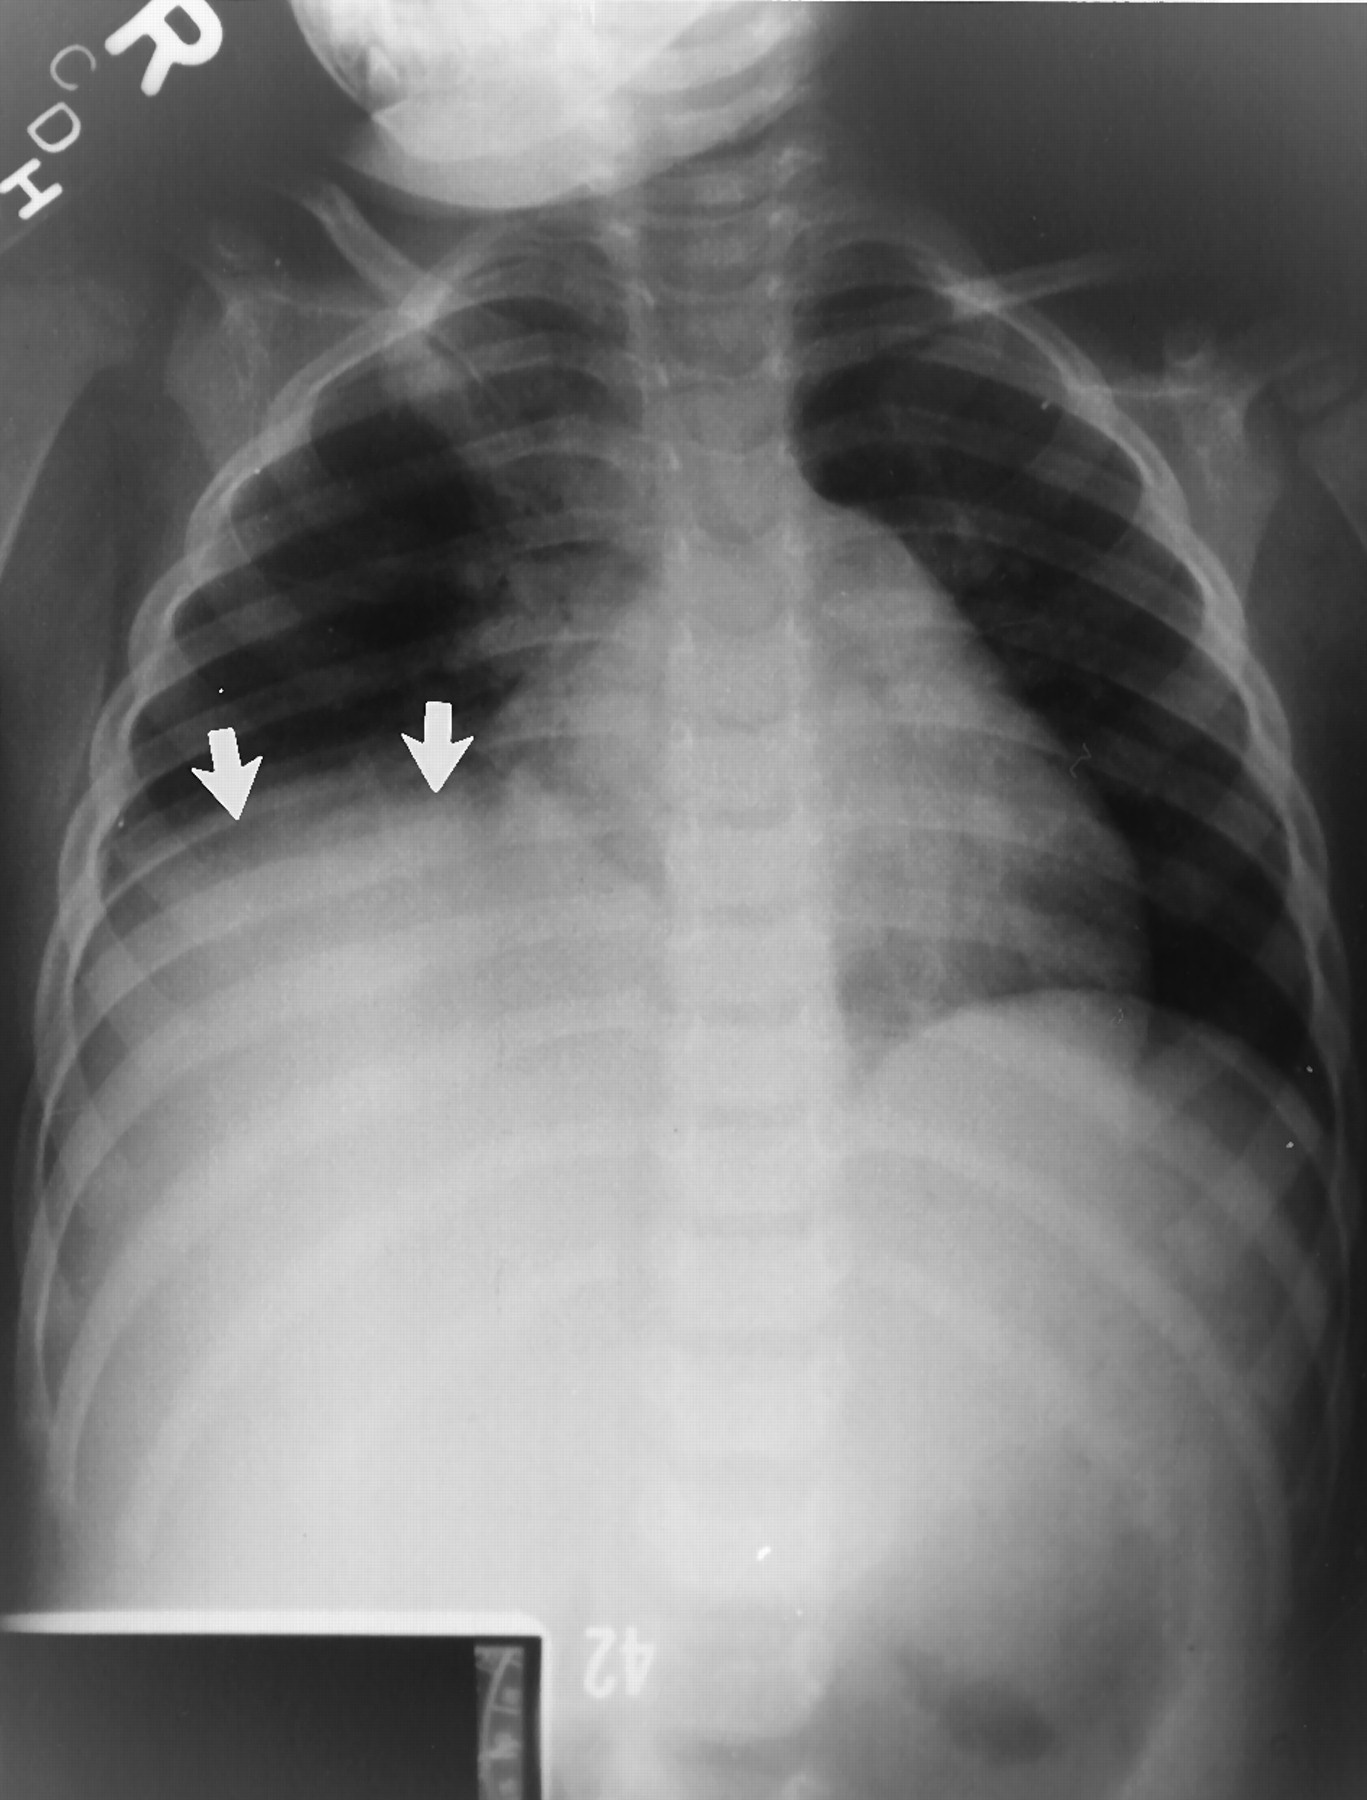

Plain abdominal radiographs in patients with toxic megacolon classically reveal thick haustral markings that do not extend across the entire lumen.

On KUB (kidney, ureter, bladder) radiographs, a classic "coffee bean sign" may be seen, indicating a sigmoid volvulus.

In the presence of a volvulus, the distal duodenum and proximal jejunum course downward in the mid abdomen. On contrast radiography, this may be seen as a “corkscrew” appearance. The lumen also becomes narrowed and may have a “beaked” appearance at the level of obstruction.